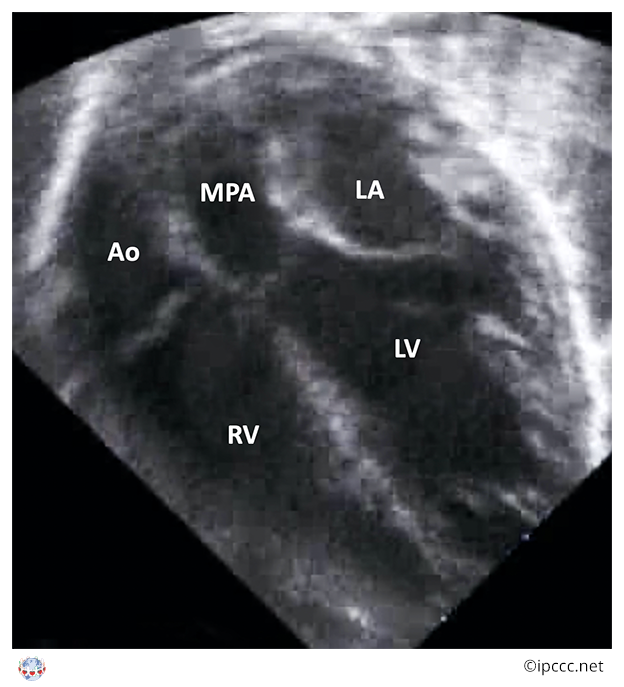

A congenital cardiovascular malformation in which the morphologically right atrium connects to the morphologically right ventricle, the morphologically left atrium connects to the morphologically left ventricle, the morphologically right ventricle connects to the aorta, the morphologically left ventricle connects to the pulmonary trunk, and a ventricular septal defect is not present.

Echocardiogram